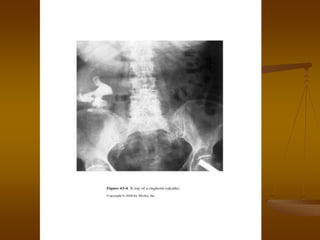

 Plain Abdominal Film/Kidney-Ureter-Bladder View

 Assessment of radio-opacity of stone

 Allows monitoring calculus progression

 Guides shockwave lithotripsy